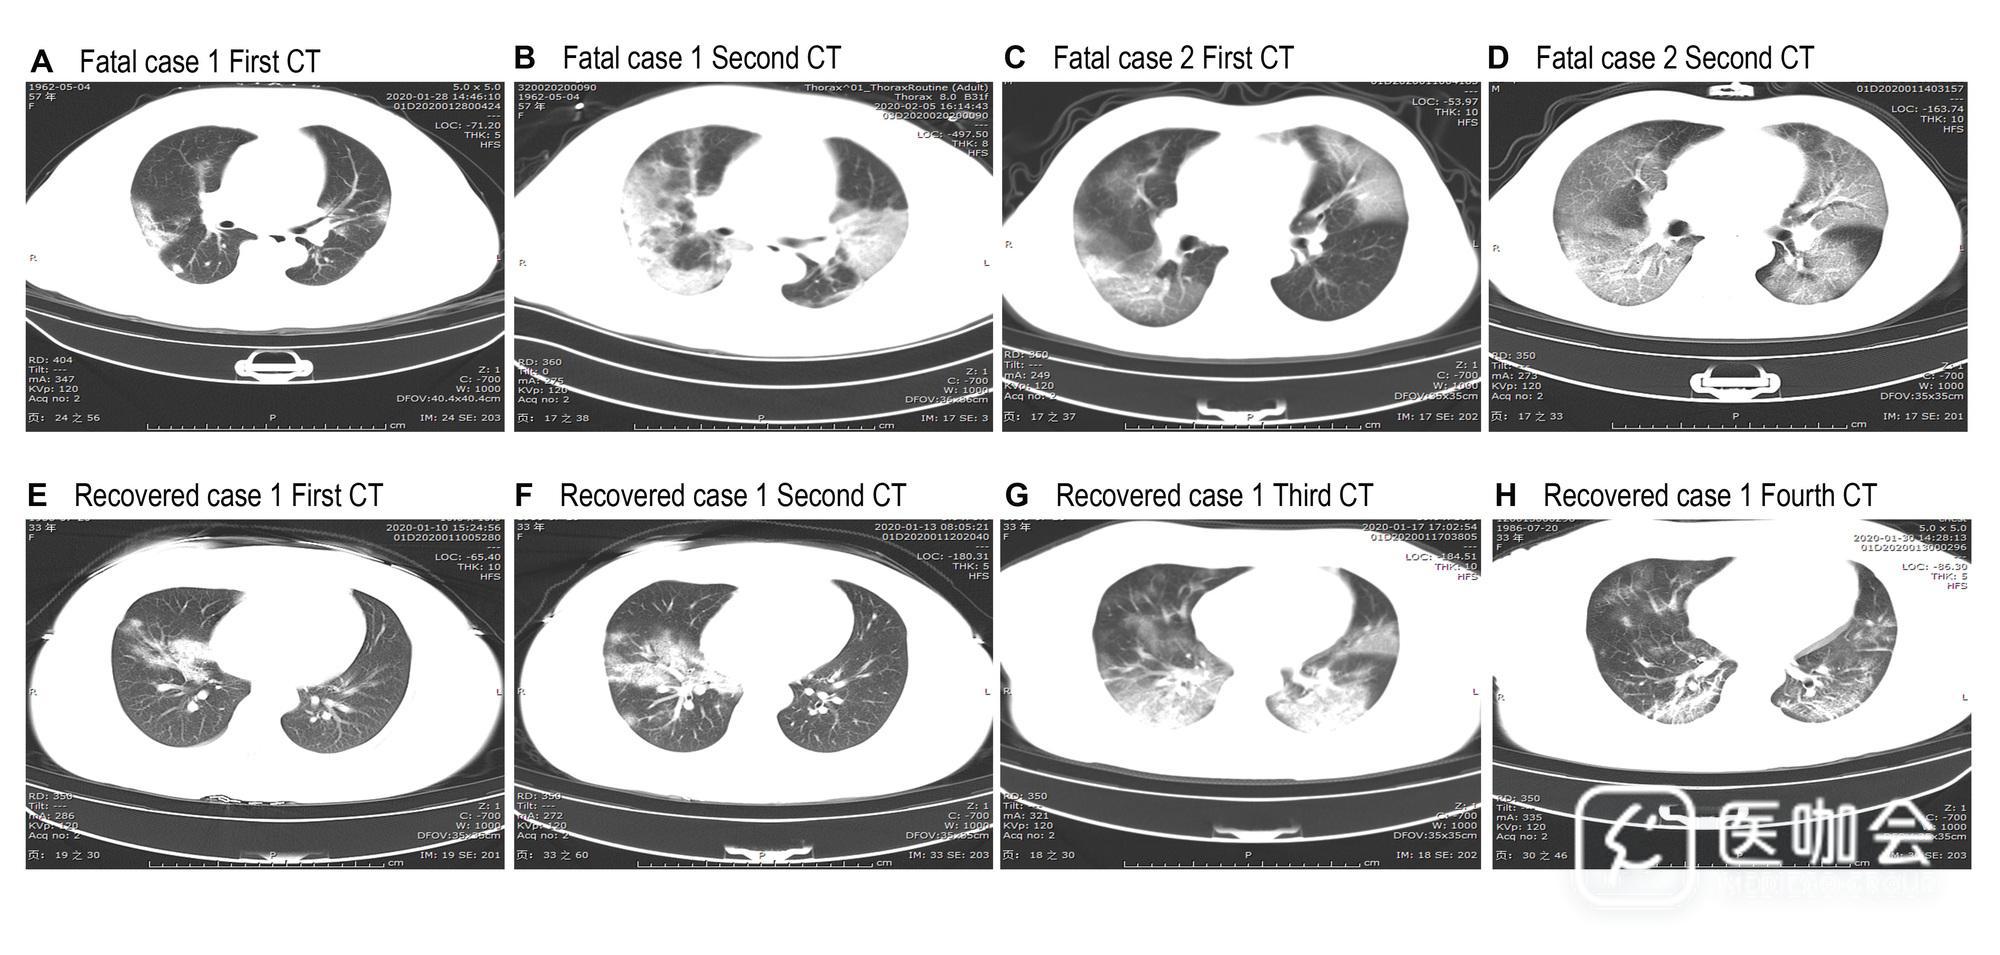

入院时,所有患者均可见胸片异常(图1);113例(100%)死亡患者和152例(94%)康复患者胸片显示双肺受累。死亡患者入院时胸部CT典型表现为双侧毛玻璃浑浊和亚节段实变(图1,A和C),然后双侧肺迅速进展为高密度大量阴影(图1,B和D)。

康复患者的典型CT表现为右中叶和下叶毛玻璃样混浊和实变(图1,E和F);然后进展为双侧毛玻璃样混浊和双侧肺实变,但右中叶实变消退(图1,G)。随访图像显示双侧毛玻璃浑浊和实变得到明显改善(图1,H)。

图1 患者肺部CT结果